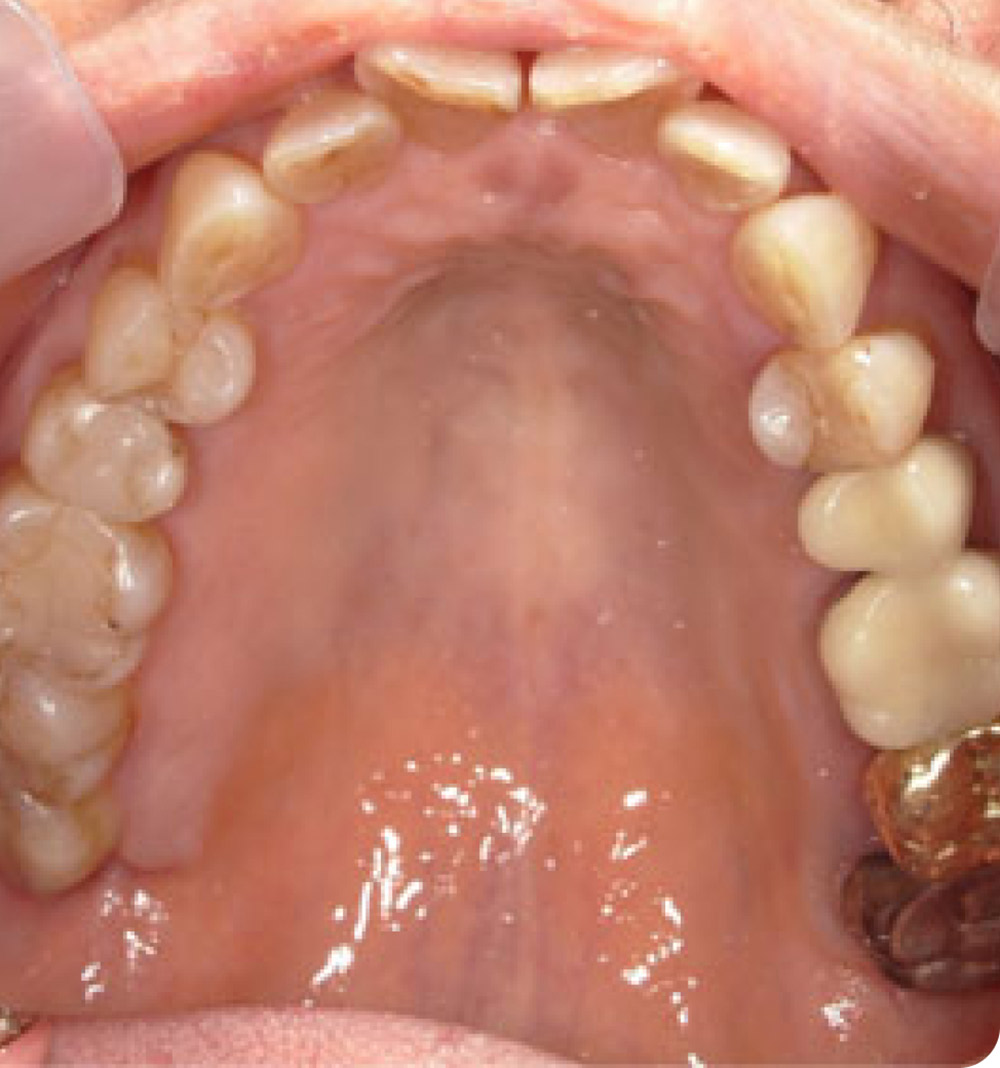

マウスピース矯正症例 術前

術前

年齢 70代(女性)

主訴 上の歯ならびがガタガタなのが気になる

期間・費用 上顎のみ8か月 264,000円(税込)